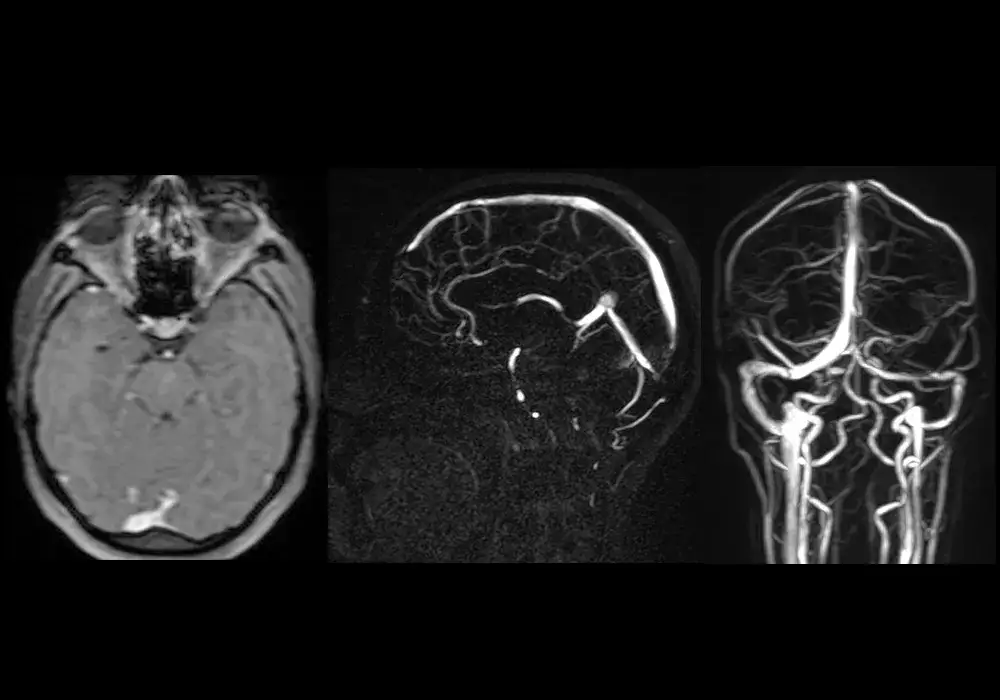

Zatoka skalista dolna jest elementem skomplikowanej sieci naczyń krwionośnych w obrębie mózgu. W neuroanatomii jej wygląd można opisać jako struktura o nieregularnym kształcie, która ma za zadanie zbierać krew z różnych obszarów mózgu. Zawiera ona również liczne połączenia z innymi zatokami, co jest istotne dla prawidłowego krążenia krwi. Warto dodać, że zatoka skalista dolna jest często przedstawiana na diagramach anatomicznych, które ilustrują jej położenie w stosunku do innych struktur mózgowych.

W celu lepszego zrozumienia jej kontekstu neuroanatomicznego, można znaleźć diagramy, które pokazują, jak zatoka skalista dolna łączy się z innymi elementami układu żylnego mózgu. Takie wizualizacje są pomocne w nauce i zrozumieniu roli tej struktury w organizmie.

W przypadku problemów zdrowotnych związanych z zatoką skalistą dolną, kluczowe jest przeprowadzenie dokładnej diagnostyki. Wśród metod diagnostycznych najczęściej stosowane są badania obrazowe, takie jak tomografia komputerowa (CT) oraz rezonans magnetyczny (MRI). Te techniki pozwalają na uzyskanie szczegółowych obrazów zatoki oraz otaczających ją struktur, co jest istotne w identyfikacji ewentualnych nieprawidłowości. Dodatkowo, w niektórych przypadkach lekarze mogą zlecić badania krwi, aby wykluczyć infekcje lub inne schorzenia, które mogą wpływać na funkcjonowanie zatoki.Po postawieniu diagnozy, leczenie zaburzeń związanych z zatoką skalistą dolną może obejmować różne podejścia. W przypadku zakrzepicy, lekarze często stosują terapię farmakologiczną, taką jak leki przeciwzakrzepowe, aby poprawić krążenie krwi. W przypadku infekcji, konieczne może być wdrożenie antybiotykoterapii. W bardziej skomplikowanych przypadkach, takich jak poważne uszkodzenia zatoki, może być konieczna interwencja chirurgiczna. Kluczowe jest, aby leczenie było dostosowane do indywidualnych potrzeb pacjenta oraz specyfiki problemu zdrowotnego.

Jakie metody diagnostyczne są stosowane w przypadku zatoki skalistej dolnej

Diagnostyka zatoki skalistej dolnej opiera się na kilku sprawdzonych metodach. Najczęściej wykorzystuje się rezonans magnetyczny (MRI), który dostarcza szczegółowych obrazów tkanek miękkich i struktur anatomicznych, co umożliwia ocenę stanu zatoki. Tomografia komputerowa (CT) jest również powszechnie stosowana, szczególnie w nagłych przypadkach, aby szybko ocenić ewentualne uszkodzenia. Dodatkowo, lekarze mogą zlecić ultrasonografię, aby ocenić przepływ krwi w obrębie zatoki oraz wykryć ewentualne zakrzepy.